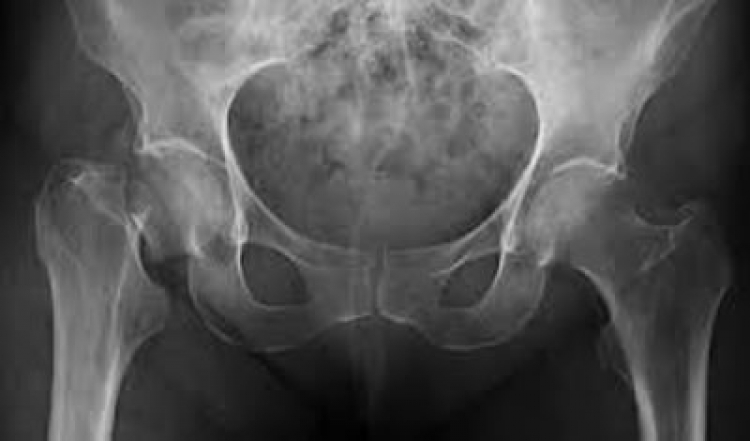

Caracterizada por una disminución de la masa ósea, lesiones de la microarquitectura del hueso, fragilidad excesiva del esqueleto y aumento del riesgo de fractura –aun a consecuencia de traumatismos menores en el contexto de las actividades cotidianas–, la osteoporosis se ha convertido en un importante problema de salud pública en China, conforme avanza el envejecimiento de la población.

En México, la prevalencia de osteoporosis en mujeres y hombres mayores de 50 años es de 17% y 9% en columna lumbar, respectivamente, y de 16% y 6% en cadera, respectivamente. Se estima que el riesgo de fractura de cadera a lo largo de la vida es de 8.5% en mujeres y 3.8% en hombres.3